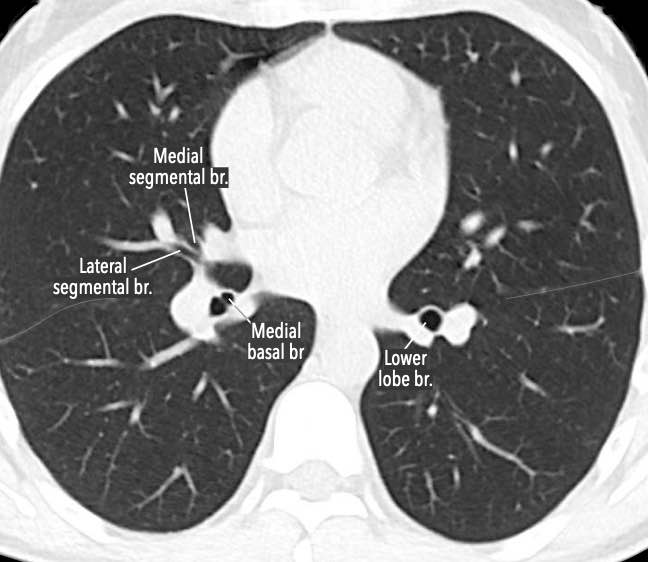

Phế quản trên CT

Cuộn qua các hình ảnh để quan sát khí quản phân chia thành phế quản chính phải và trái, sau đó tiếp tục phân chia thành các phế quản thùy và phế quản phân thùy.